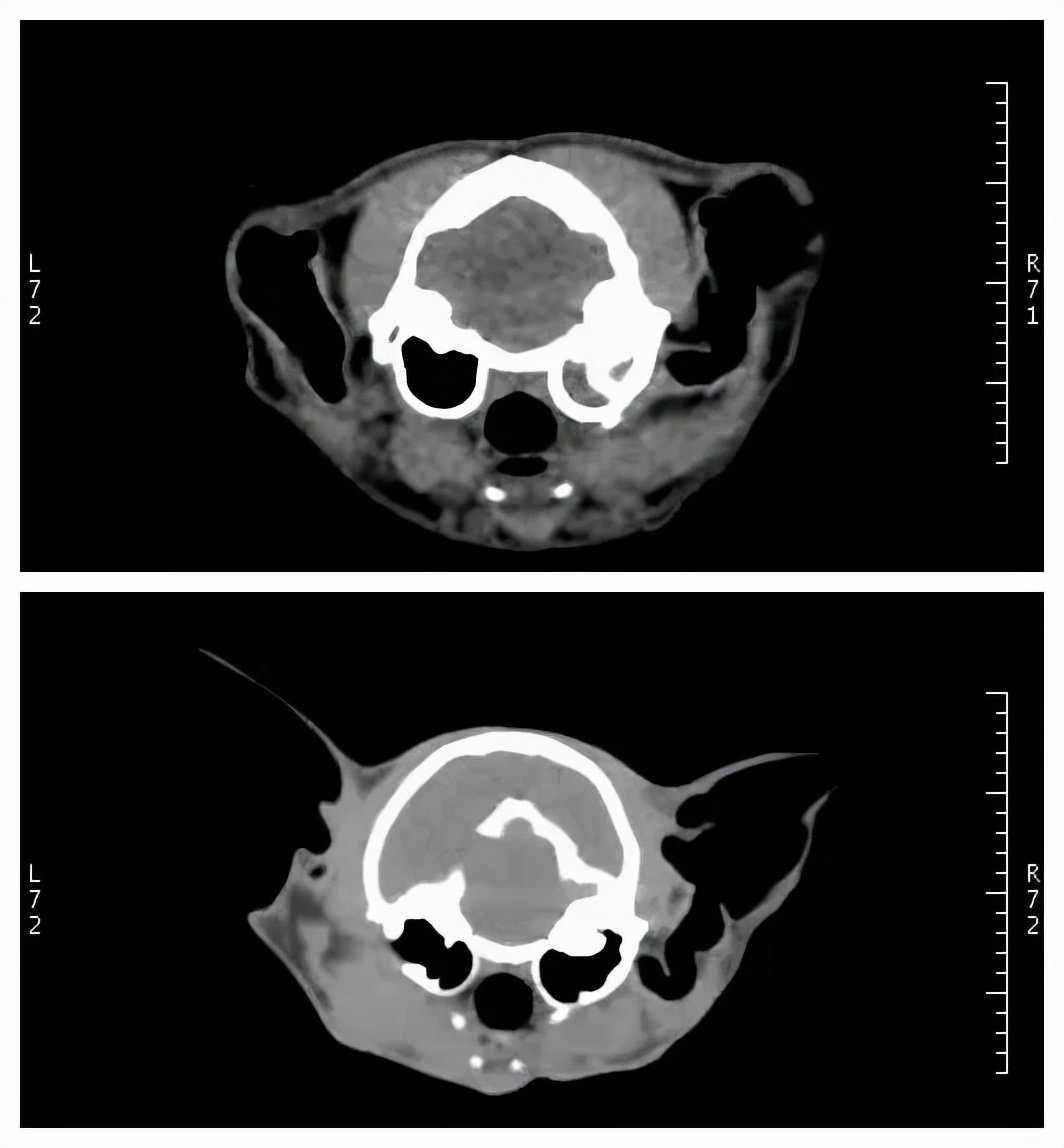

检查结果很快出来。根据CT检查结果,黄医生发现,珠珠存在 中耳炎、鼓室积液 等症状。

珠珠的CT检查结果:可看到有中耳炎、鼓室有积液等情况